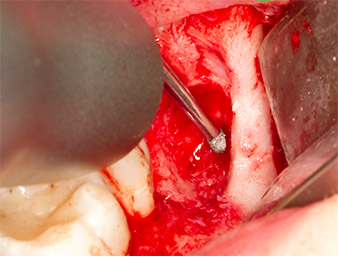

Sous bloc nerveux et anesthésie locale, le site d’intervention est ouvert et les tissus mous sont exposés afin d’accéder à la zone rétromolaire buccale (Fig. 3).

Le tissu recouvrant le reste radiculaire n’est pas entièrement ossifié et est essentiellement constitué de tissu de granulation modifié par l'inflammation (Fig. 4).

Pour obtenir un matériau autogène en vue du traitement ultérieur de la plaie, des fragments osseux sains sont collectés autour du reste radiculaire à l'aide d’un insert piézochirurgical (Piezomed B5) (Fig. 5).